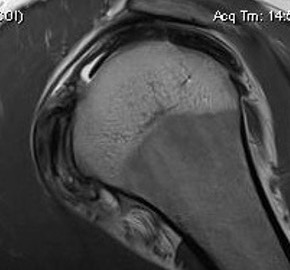

MRI

CT

Lesser tuberosity can become overgrown